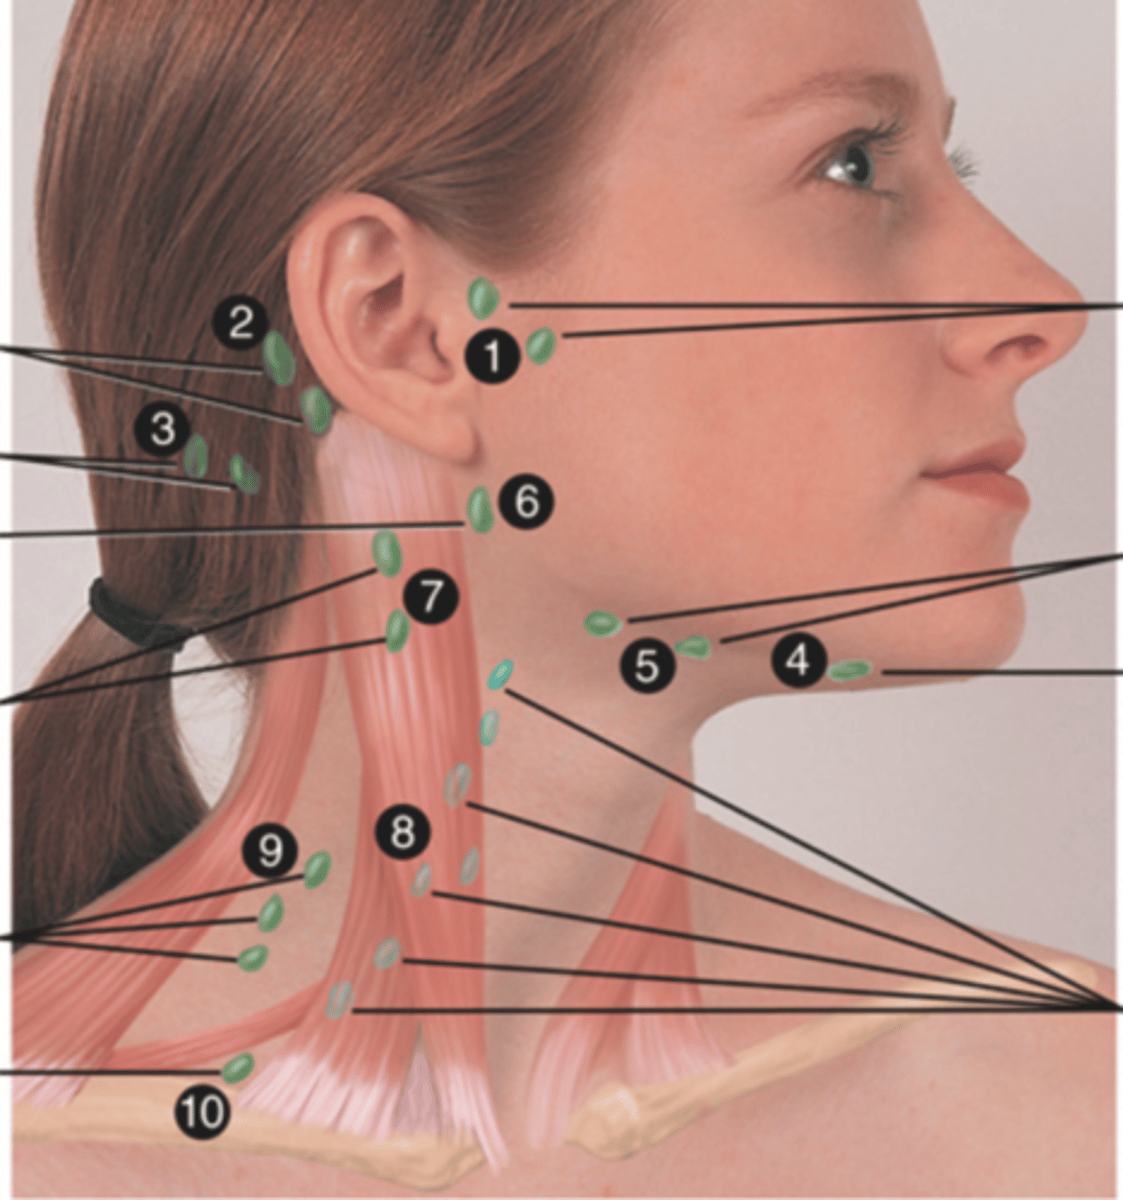

Major Lymph Nodes in the Neck (FUN!)

(Party People Often Sell Sardines Just So Dogs Pee Silver)

Preauricular Lymph Node

Lymph node in front of the ear (1)

Posterior Auricular Lymph Node

Lymph node behind the ear (2)

Occipital Lymph Node

Lymph node at the base of skull (3)

Submental Lymph Node

Lymph node under the chin (4)

Submandibular Lymph Node

Lymph node along base of mandible (5)

Jugulodigastric (Tonsil) Lymph Node

Lymph node under the angle of the mandible (6)

Superficial Cervical Lymph Node

Lymph node overlying the sternomastoid muscle (7); can feel enlarged even when there are no problems

Deep Cervical Chain Lymph Node

Lymph node located on the posterior triangle of the neck (8)

Posterior Cervical Lymph Node

Lymph node in the posterior triangle along the edge of the trapezius muscle (9)

Supraclavicular Lymph Node

Lymph node just above and behind the clavicle, at the sternomastoid muscle (10)